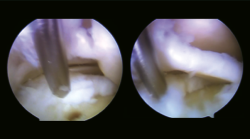

Se solicitó resonancia magnética (RM) y tomografía axial computarizada (TAC) del tobillo afecto a los 6 meses del traumatismo, en las que se observó una lesión osteocondral en la cúpula astragalina de 15 × 11 mm (diámetro anteroposterior y medial-lateral) según la RM y de 9 × 7 mm según la TAC (Figura 2). No se observó lesión capsuloligamentosa. Sí que se detectaron pequeños cuerpos libres en el receso capsular posteroexterno y anteromedial.

Figura 2. Imágenes de resonancia magnética (RM) en T2 (corte sagital y coronal). Imagen de la tomografía axial computarizada (TAC), corte coronal. Se observa una lesión osteocondral en la cúpula astragalina de 15 × 11 mm (diámetro anteroposterior y medial-lateral) según la RM y de 9 × 7 mm según la TAC.